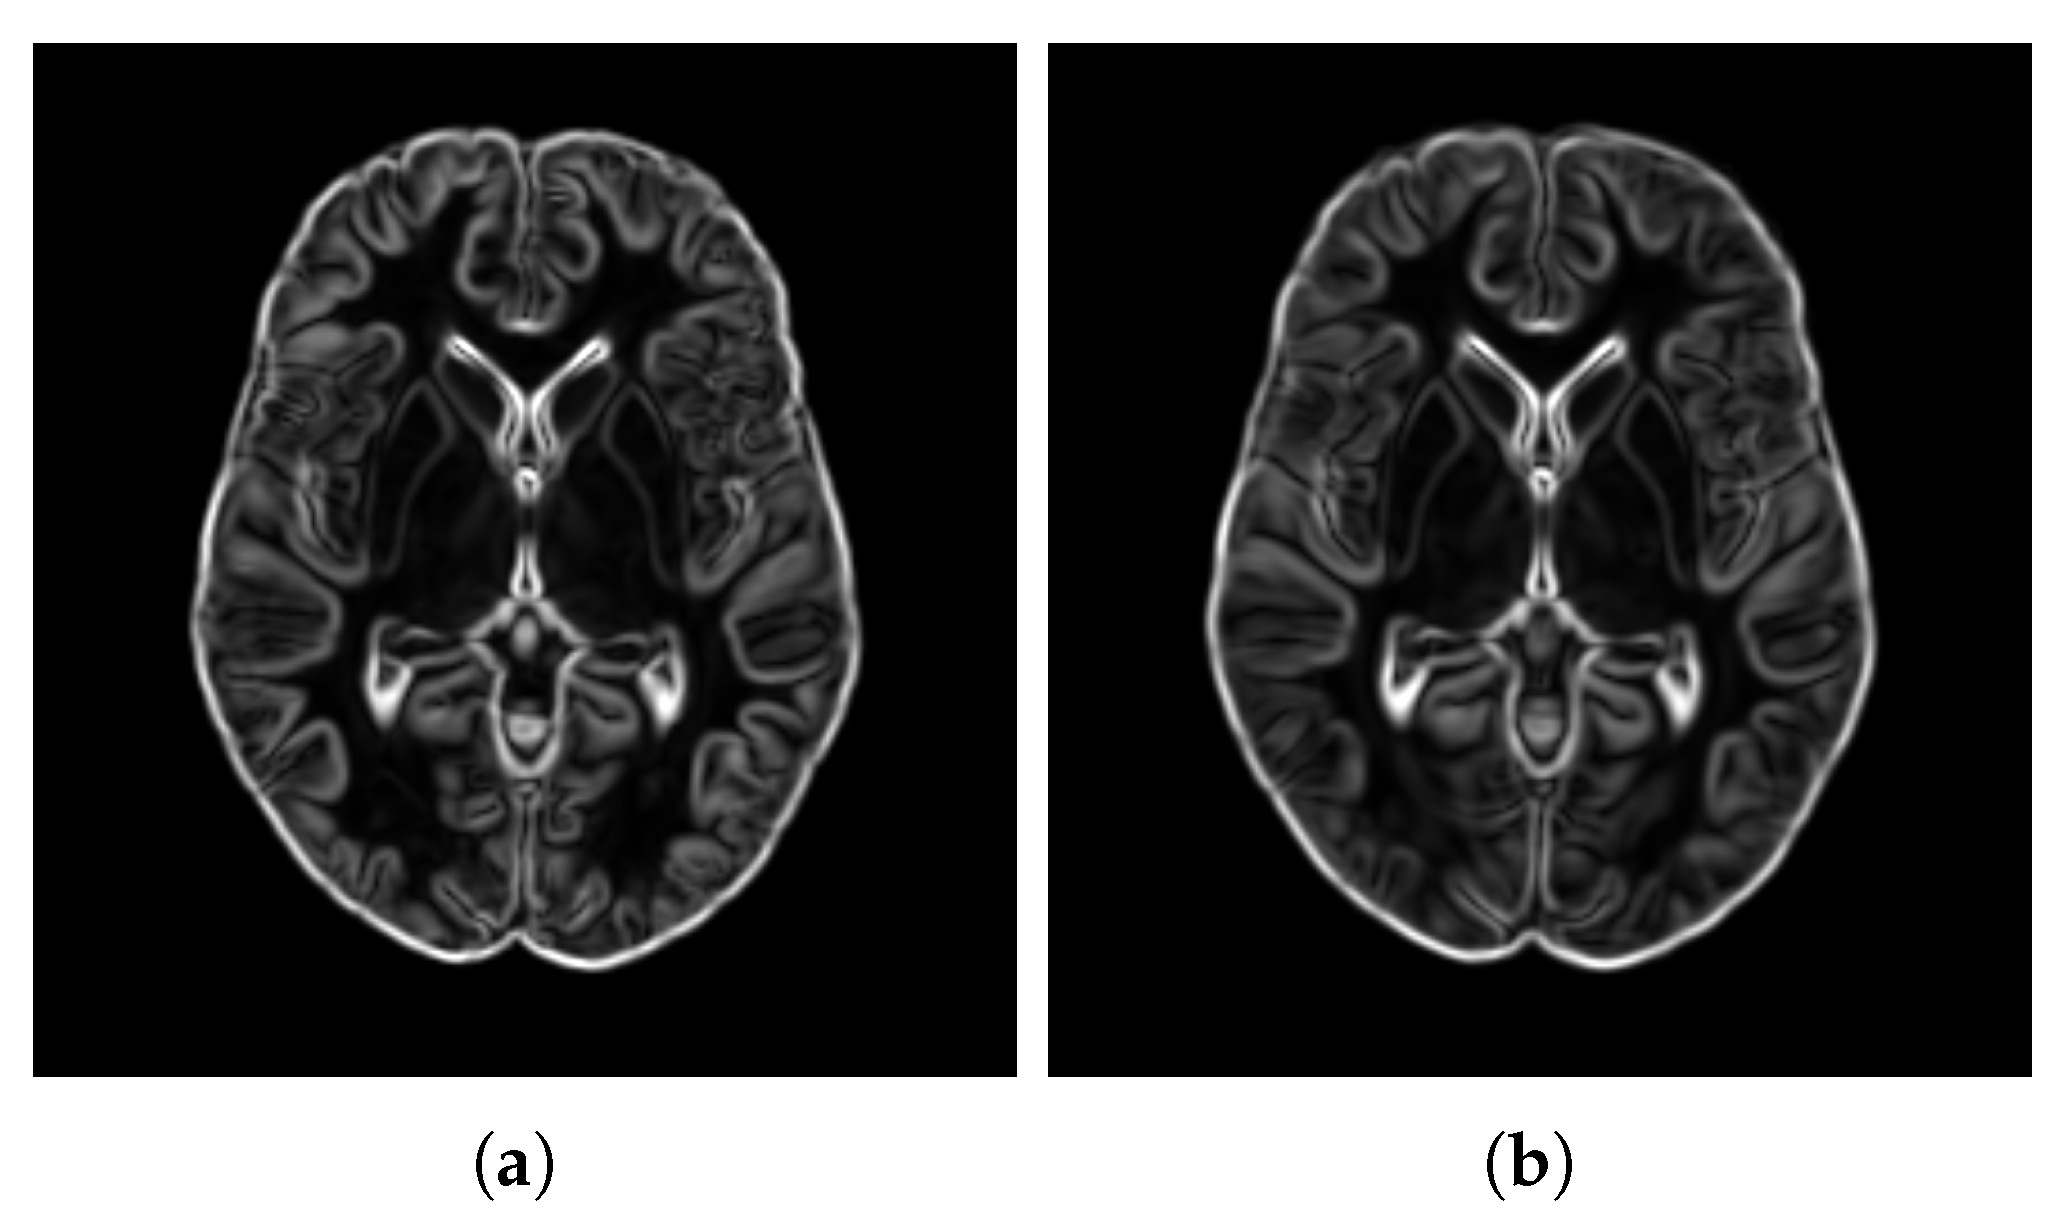

- SharpnessTo evaluate the sharpness and edge definition of the templates, we computed the magnitude of the gradient for each voxel. Sharp edges and well-defined details correspond to regions with rapid changes in intensity, which are reflected in high gradient magnitudes. To assess the overall sharpness, we averaged the gradient magnitudes across all voxels in the template. This metric—as used in Wang et al. [53]—which we refer to as Average Gradient Magnitude (), quantifies the overall sharpness of the template:where is the intensity value of the template at voxel index v, ∇ is the gradient operator, and M is the total number of voxels in the template.

- SharpnessFigure 14 visualizes the gradient magnitude for and , with their corresponding values summarized in Table 4. The value for (60.958) was higher than that of (55.175). The higher value for indicates that the patch-based approach resulted in a template with sharper edges compared with the voxel-based averaging method. This finding suggests that patch-based estimation of template intensity can lead to sharper templates compared with traditional voxel-based averaging.